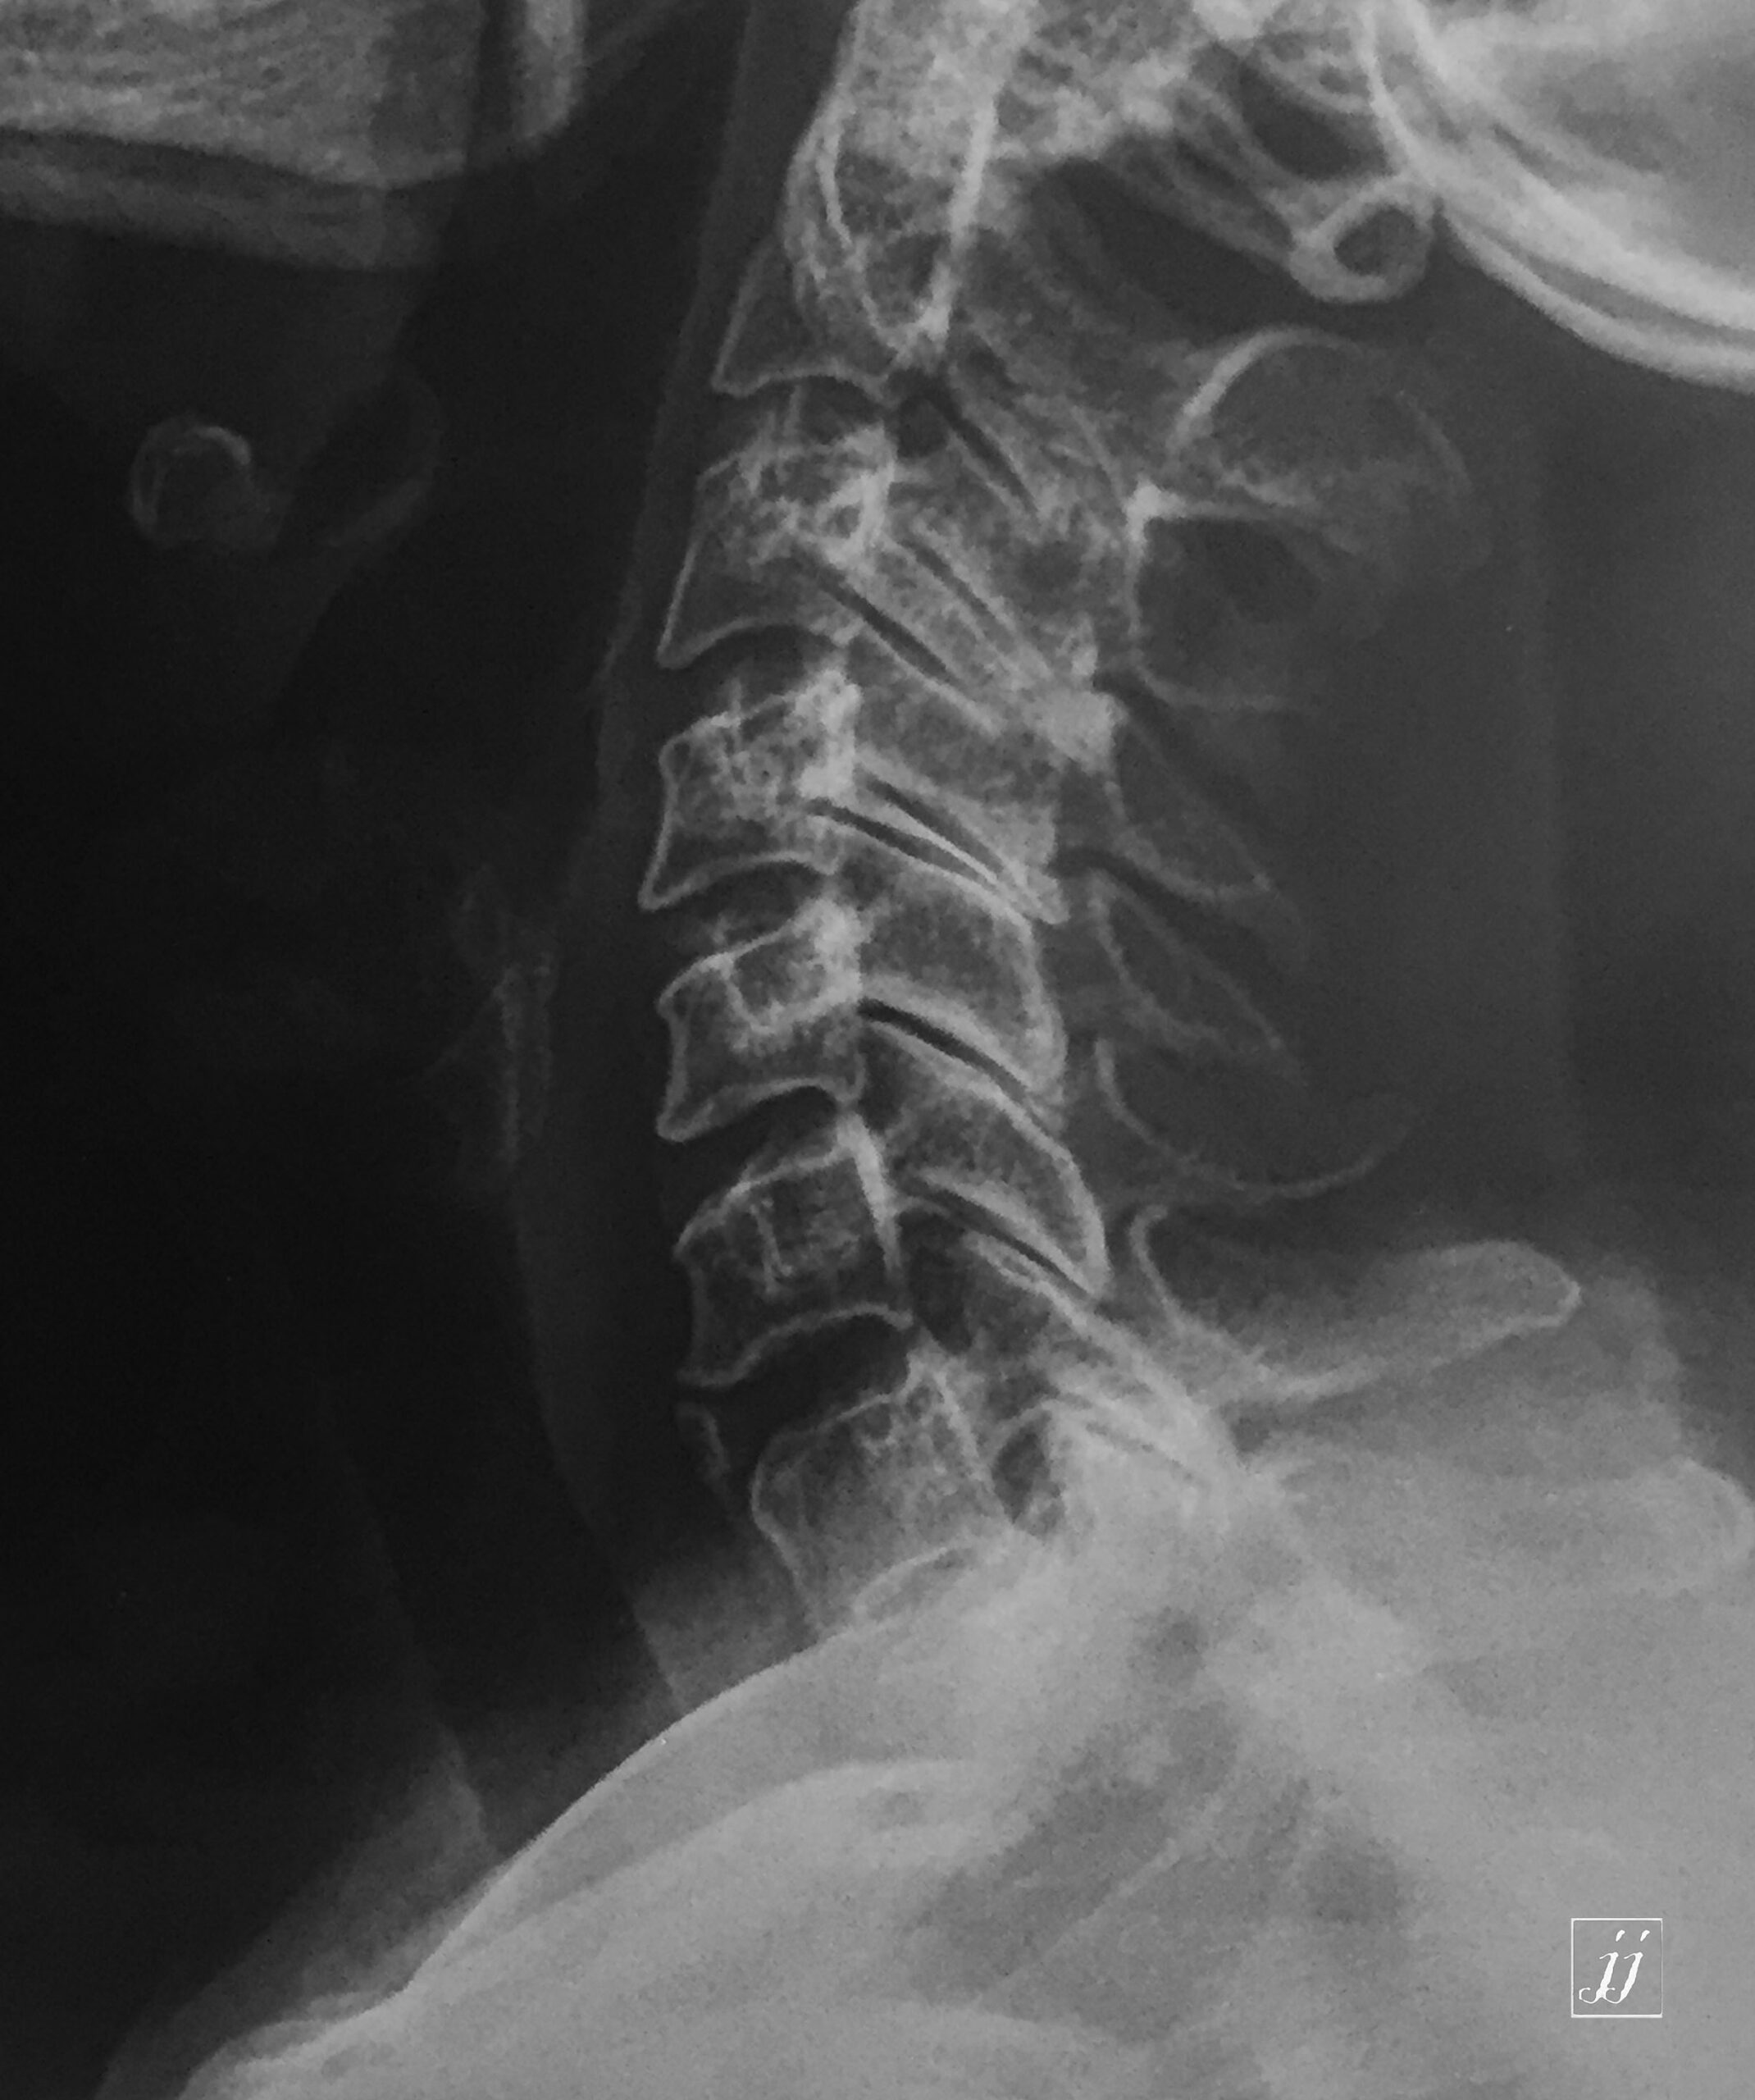

Spine- anterior osteophyte (1)